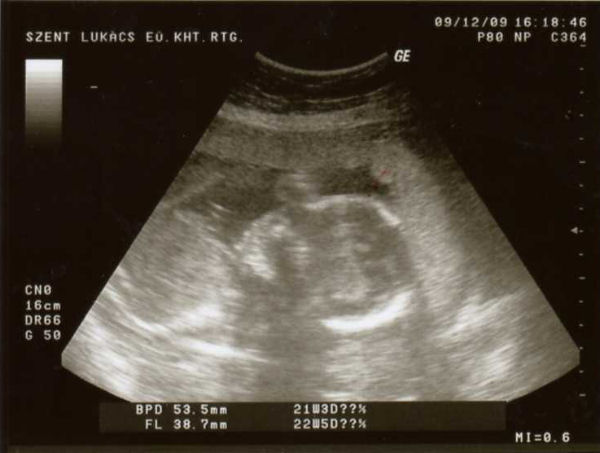

Megvagyunk a 4D-vel, minden rendben van. A mért adatok alapján 6 nappal fiatalabb mint a mensis számítás alapján.

Ébren volt, az egyik keze végig ott volt az arca környékén, nyújtogatta az ujjait, olyan volt mintha számolt volna. Aztán egyszer csak az egyik lábát is odatolta a fejéhez. Nyitogatta a száját (kortyolt), és ásított is.

Sajna a nemét 1000 %-osra ismét nem tudta megmondani, mert a lábait nagyon maga alá húzta. Többször is visszament hogy megnézze, aztán a végén azt mondta hogy inkább csajszinak tűnik, de nem meri totál biztosra mondani.

Úgyhogy a lényeg hogy minden rendben van, a hasi szervek, az agy, a méretek-arányok, stb. stb.

Aszonta a doki nő, hogy a legjobb a 30. hét környékén csináltatni a 4D-t, mert az arca ekkor néz ki szinte 100 %-ban úgy mint a születéskor. Utána már azért nem, mert annyira kicsi lesz a hely odabent hogy gyűrődik, összenyomódik az arcocskája.